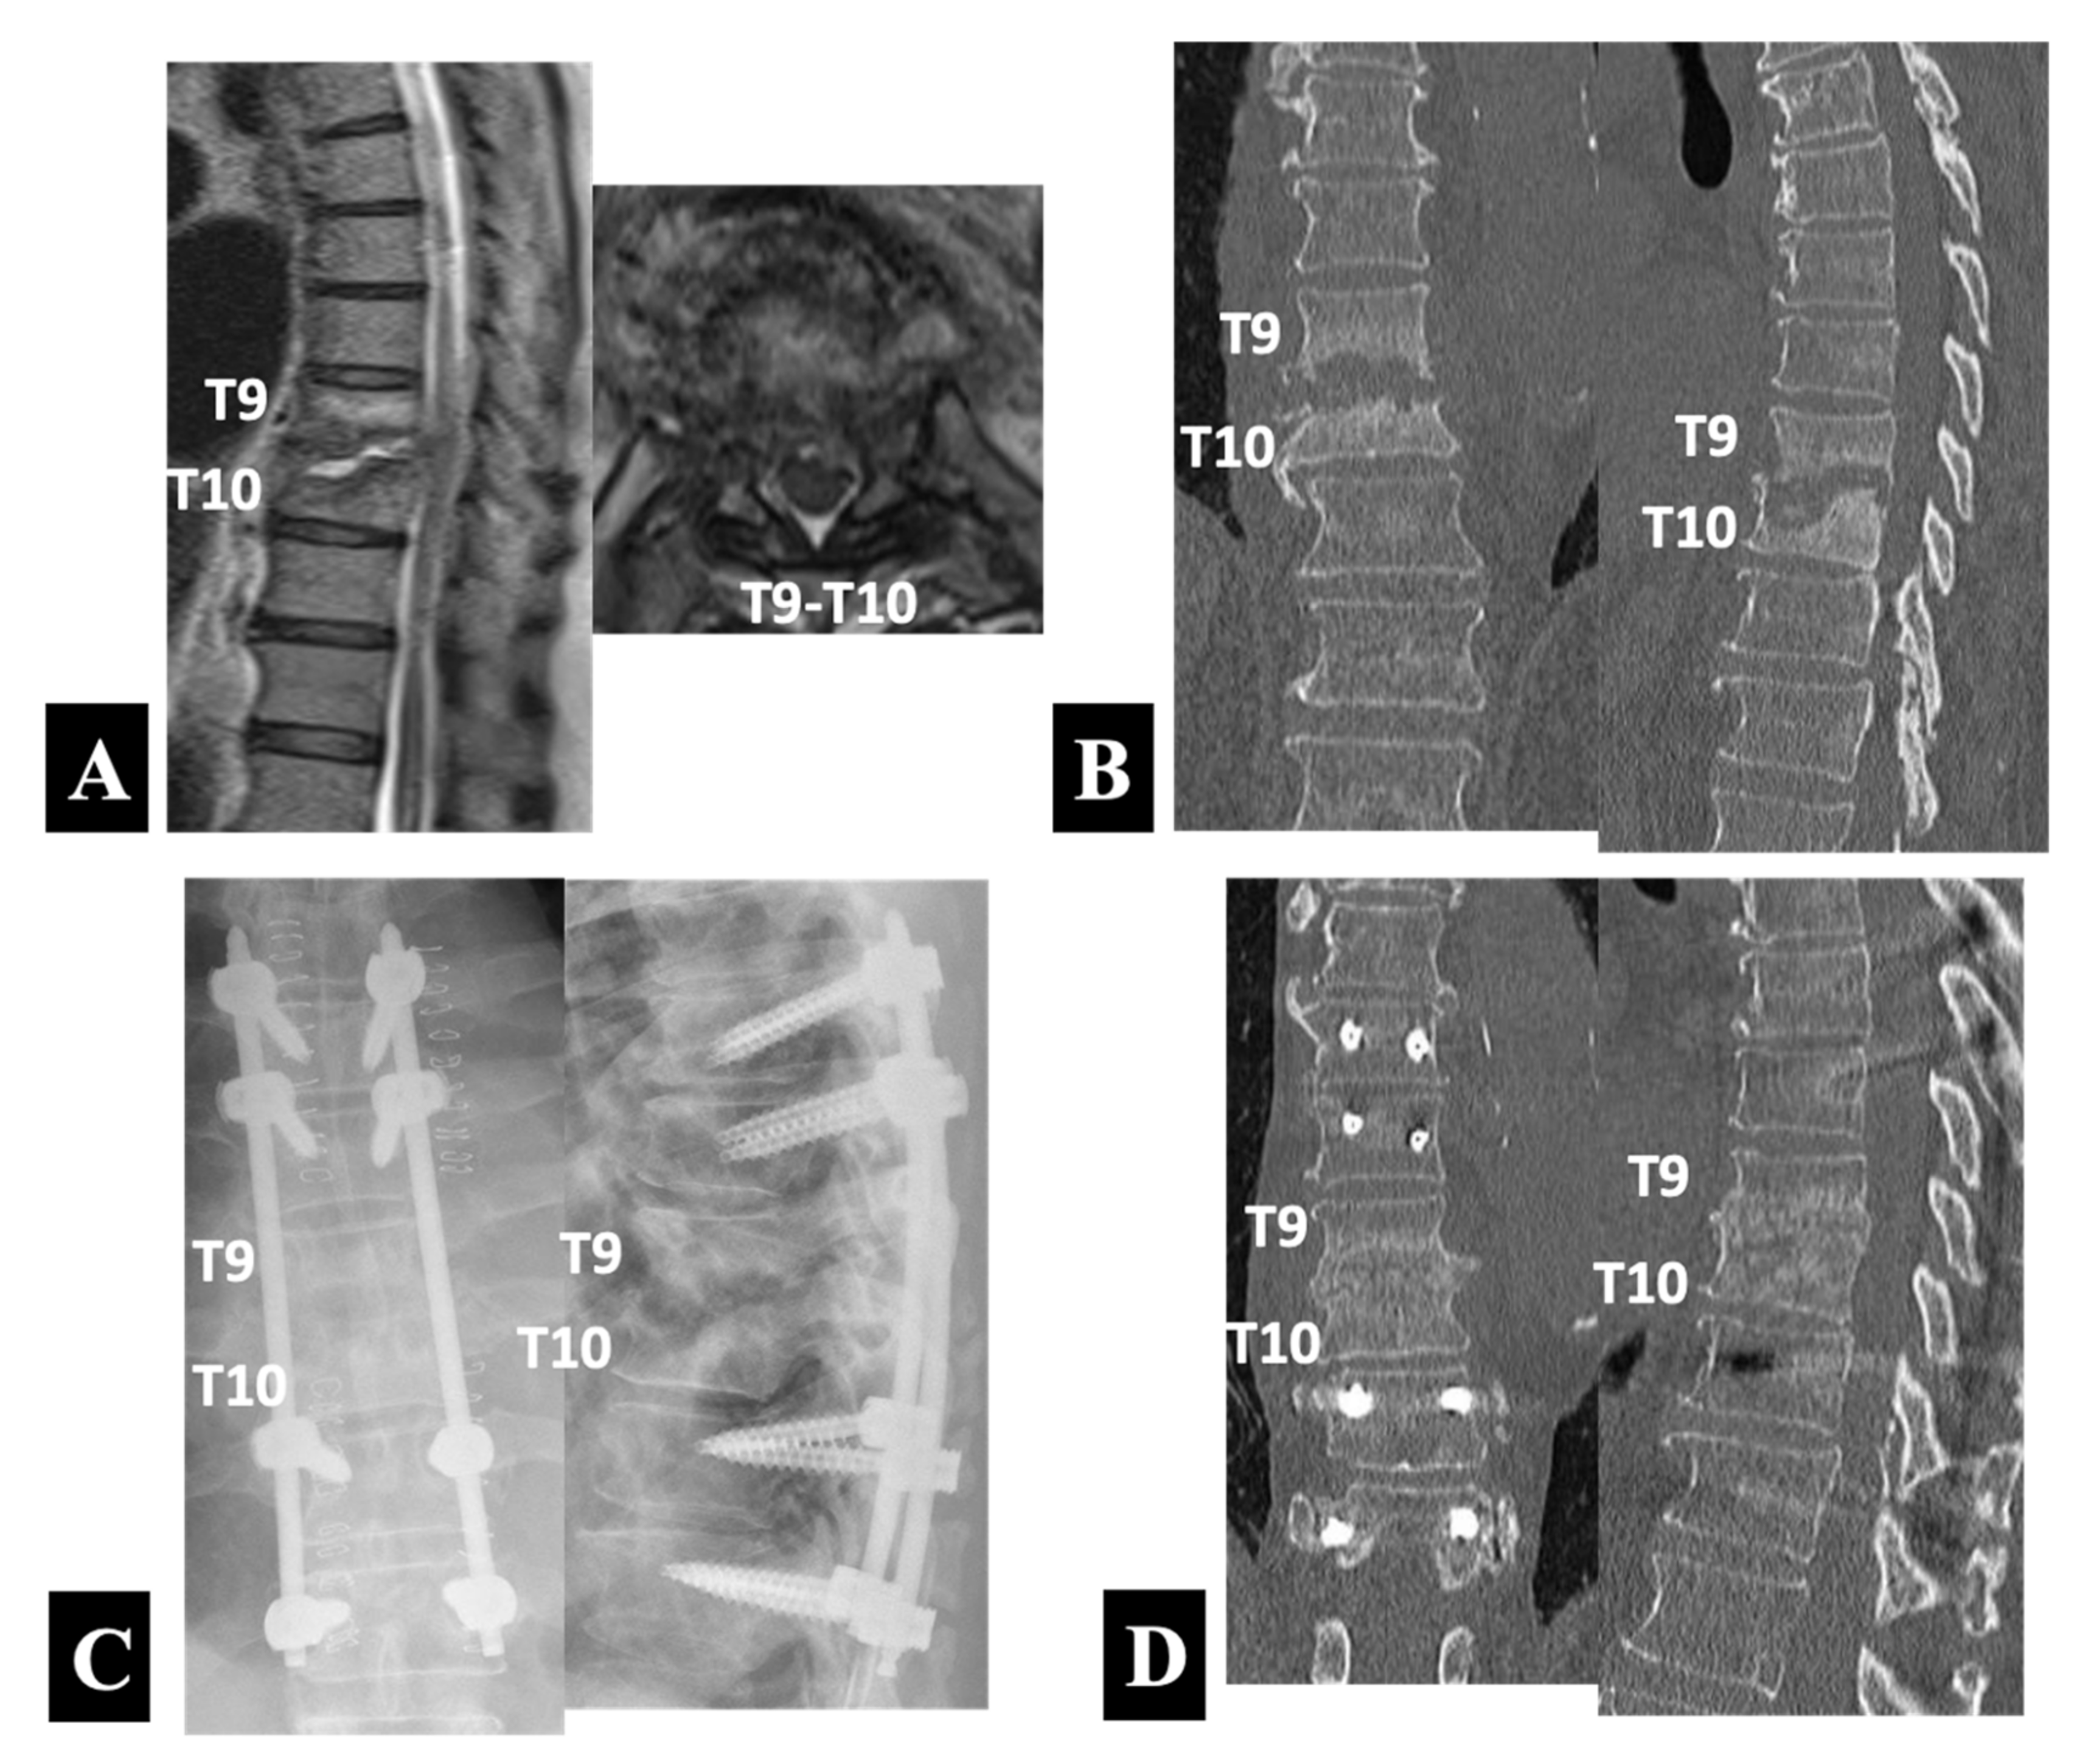

Figure 3. Preoperative sagittal and axial T2-weighted MRIs (A) and coronal and sagittal reformatted CT images (B) in a 66 year old neurologically intact man with pyogenic spondylodiscitis at T9 and T10. He underwent PPS–rod fixation alone with PPSs placed into the unaffected vertebrae of the T7 and T8 rostrally and the T11 and T12 caudally (Group 1-B) as shown by anteroposterior and lateral plain radiographs taken immediately after surgery (C) and coronal and sagittal reformatted CT images 9 months postoperatively (D).

A 66 year old man presented with severe posture-related back pain and fever. He had been hospitalized to undergo conservative treatment at another institution before being referred to the university hospital for surgery. He had comorbid illnesses such as diabetes mellitus and atrial fibrillation. A medical examination after admission diagnosed his spondylodiscitis as a bloodstream infection from infective endocarditis. The blood culture, which yielded Gram-positive cocci, followed by a sensitivity test determined the use of linezolid as the most specific and least toxic antibiotic agent. The T2-weighted MRI scans (Figure 3A) showed abnormal signal intensities in the peridiscal area of the T9 and T10 vertebral bodies with loss of definition of the endplates, which accompanied abscess formation in the T9–T10 disc space. Consistent with a normal neurologic examination, the MRI scans revealed only a mild cord compression. The CT scans (Figure 3B) demonstrated advanced destruction of the T9 and T10 vertebral bodies involving the endplates.

Because of the absence of neurological symptoms and signs, he underwent PPS–rod fixation alone with PPSs placed into the unaffected vertebrae of the T7 and T8 rostrally and the T11 and T12 caudally. The radiographs taken immediately after the operation (Figure 3C) showed the posterior instrumentation construct. Two months after the operation, he underwent mitral valve repair for infective endocarditis. The CT scans at 9 months follow up (Figure 3D) confirmed a progressive bone formation without an increase in local kyphosis at the affected T9–T10 intervertebral level.